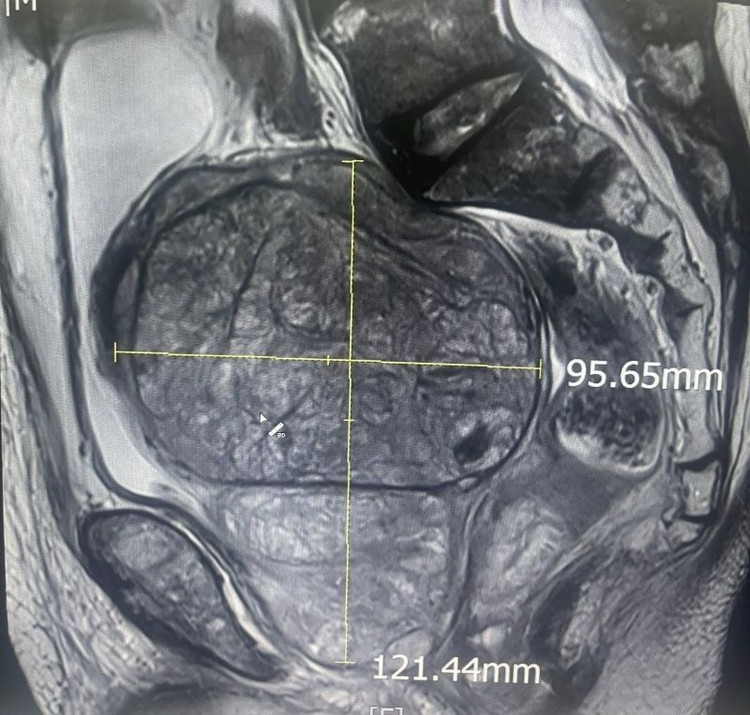

tien-liet1.jpg

Kích thước khối u khổng lồ trên phim chụp - Ảnh BVCC